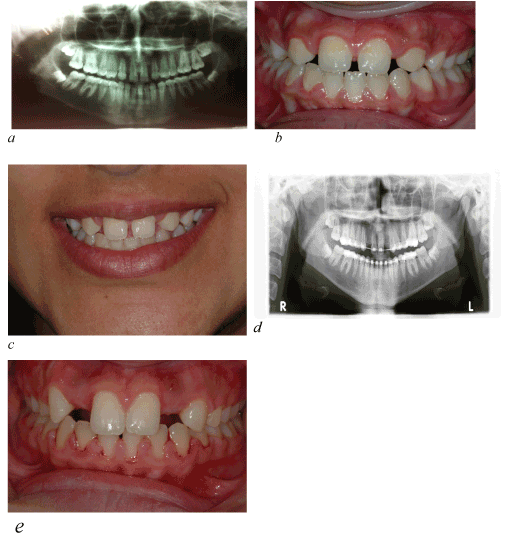

The orthodontic approach is, in the authors’ opinion, the most conservative approach and is favorable if a patient meets certain requirements. These requirements are (1) malocclusion and (2) size, shape, and color of the canines (Figure 1).

Figure 1a-c. male aged 11y3m, comes at our observation completion of permanent eruption, showing upper cuspid just in lateral incisors position

If all this recontouring requires a significant amount of reduction of enamel, problems may occur. One of the problems that can be faced is that a patient experiences dental hypersensitivity, although Zacchrison et al. has shown that if all these reductions are performed using diamond instruments with abundant water spray cooling on young teeth, there are no long-term changes in tooth sensitivity. If dentin is exposed, an adjunctive restoration may be necessary [15] (Figure 2).

Figure 2. at the End of orthodontic treatment

Figure 3a-d. After orthodontic space closure and debonding, a perfect plaque control is required, in order to obtain and maintain a good gingival profile.

The bracket placement in canine substitution cases is different. The bracket is not placed with the incisal edge of the canine as a reference but with the gingival margin as the guide. The gingival zeniths of the lateral incisors should be 0.5 to 1 mm lower than the central incisors, so the canine bracket has to be placed accordingly [15]. To make the final decision if a patient is suitable for the orthodontic approach and to anticipate if additional restorations may be necessary, the authors strongly suggest a carefully executed treatment plan (Figure 4,5).

Figure 4a-b. Two-year follow-up anterior view

Figure 5a-b. Two-year follow-up left and right